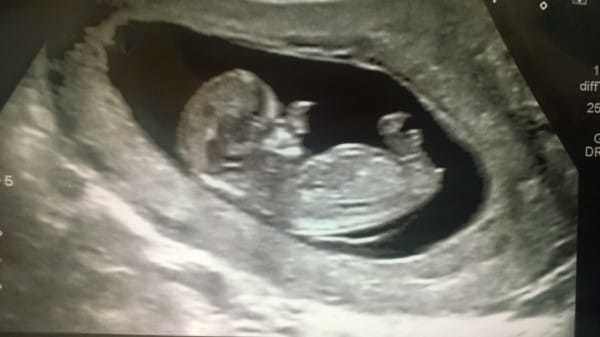

Amy poole, ikinci bebeğine hamileydi. ancak bu sıradan bir hamilelik değildi. doktora gidip ultrasona girdiğinde, hayatının şokunu yaşadı. doktor, 20 haftalık bebeğim yüzünde hiçte normal olmayan bir şeyler görmüştü.

Minik ollie 'sefalosel' hastası. sefalosel ya da beyin fıtığı; beyin dokusunun kafa tasındaki bir açıklıktan dışarıya çıkmasıdır. anne rahmindeki gelişim süreci boyunca kafanın arkasındaki ya da önündeki bir açıklık sonucu bu durum gerçekleşebilir.

Ultrason ile kafa tasının kenarında bir kitle görülmesi durumunda ve yüksek ms-afp değeleri varlığında tanıdan şüphelenilir.